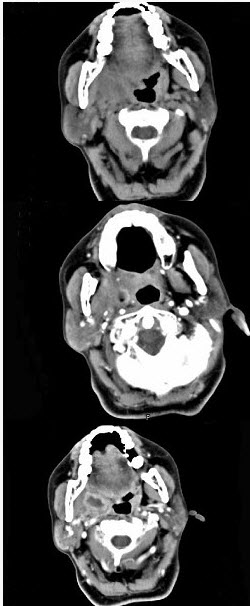

ct平扫横断面示左侧咽侧壁及咽旁间隙软组织肿胀增厚,左侧咽旁间隙